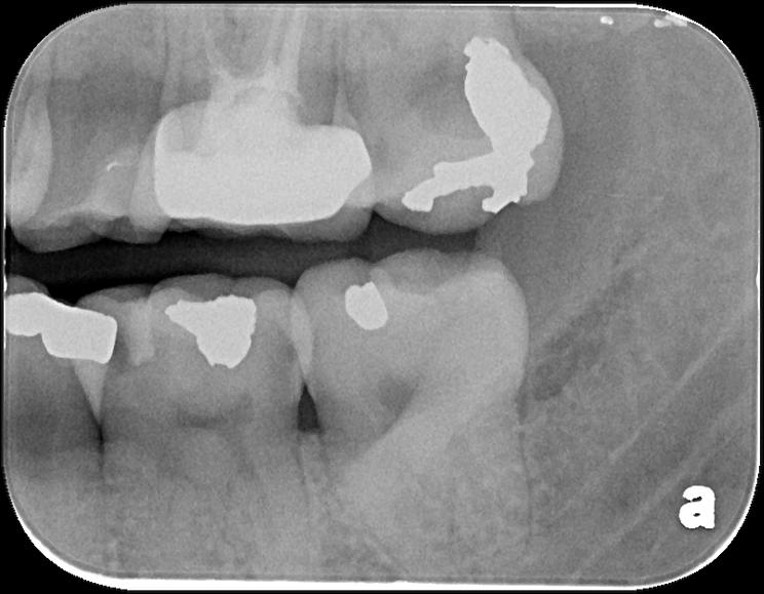

治療前,頰側牙齒蛀牙

X光邊緣完整